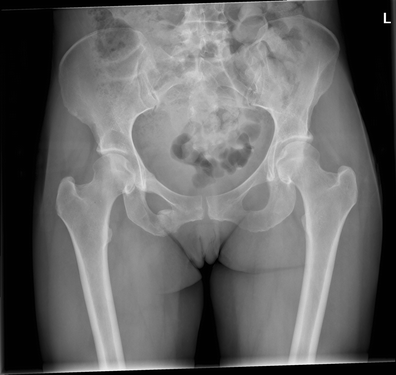

27+ Pubic Bone Stress Fracture UK. The pubis, the ischium, and the ilium. The pubis bone is one of three bones that make up the pelvis.

In osteitis pubis it becomes inflamed. The left and right pubic bones are each made up of three sections, a superior ramus, inferior ramus, and a body. A report of six cases.

Stress fractures are bones injured by overuse. Prior history of stress fracture1,5. Instead of resulting from a single severe impact, stress fractures are the result of accumulated injury from repeated submaximal loading, such as running or jumping. Stress injuries can be found in the shin bone, foot, heel, hip and lower back.